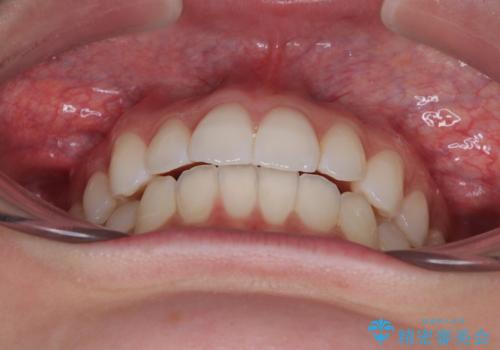

治療途中、出産や転居があり、2年ほど治療期間が長くなってしまいましたが、前歯の歯並びや飛び出した感覚を無事に改善させることができました。

インビザラインによる上下歯列の側方拡大と後方移動、必要に応じてIPR(歯と歯の間を削る)によりスペースの獲得により歯列を整えることとしました。

【モニター】前に傾斜した前歯 インビザラインでスッキリとした口元に